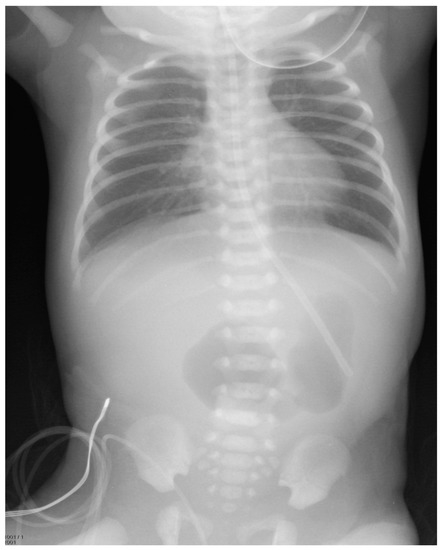

Figure 1.

Plain abdominal radiograph taken soon after birth, showing a double-bubble in the lower abdomen.